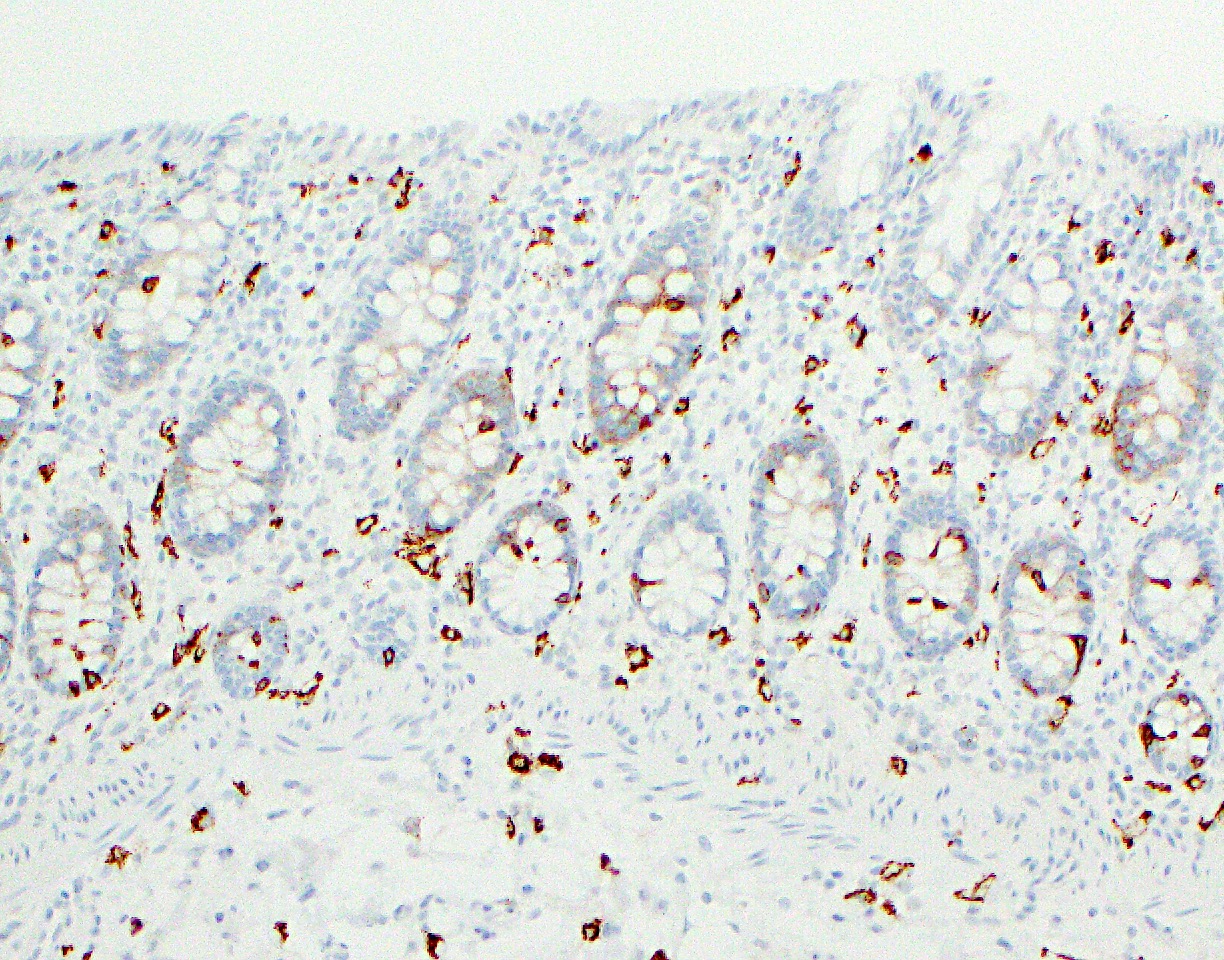

Positive stains

- Goblet cells: MUC2, depending on their surface or crypt location in the mucosa; periodic acid Schiff (PAS), PAS diastase (PASD), mucicarmine and Alcian blue also stain the mucin in goblet cells (Histopathology 2000;37:561)

- Enteroendocrine cells: synaptophysin, chromogranin, neuron specific enolase (NSE) and pankeratin AE1 / AE3

- Paneth cells: AE1 / AE3

- Macrophages: CD68, CD163, HAM56, MAC387, lysozyme and alpha-1 antitrypsin

- Mast cells: KIT, tryptase